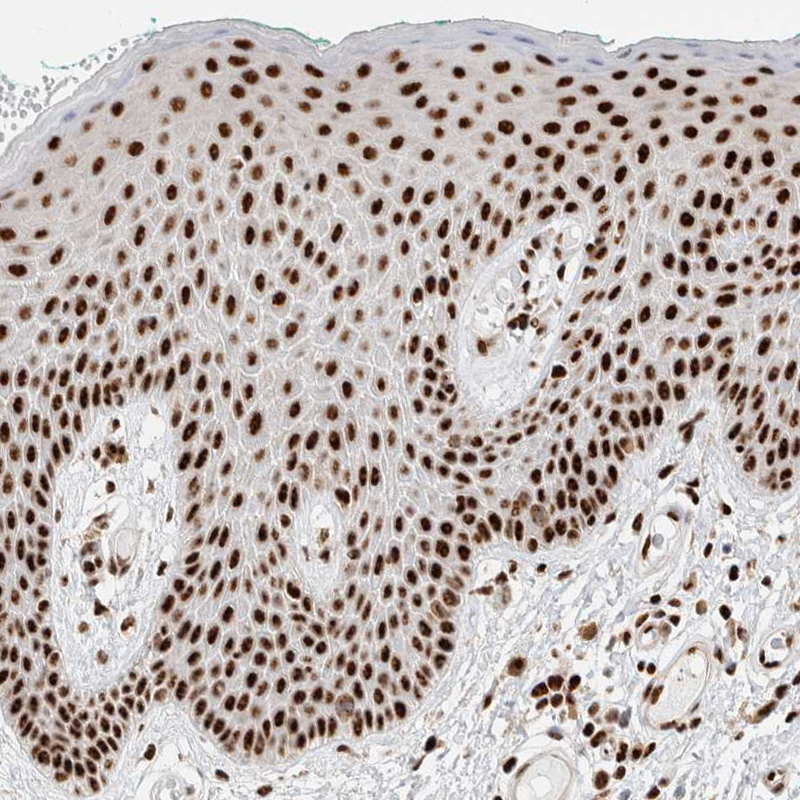

Immunohistochemistry analysis in human fallopian tube and liver tissues using HPA024677 antibody. Corresponding ID3 RNA-seq data are presented for the same tissues.